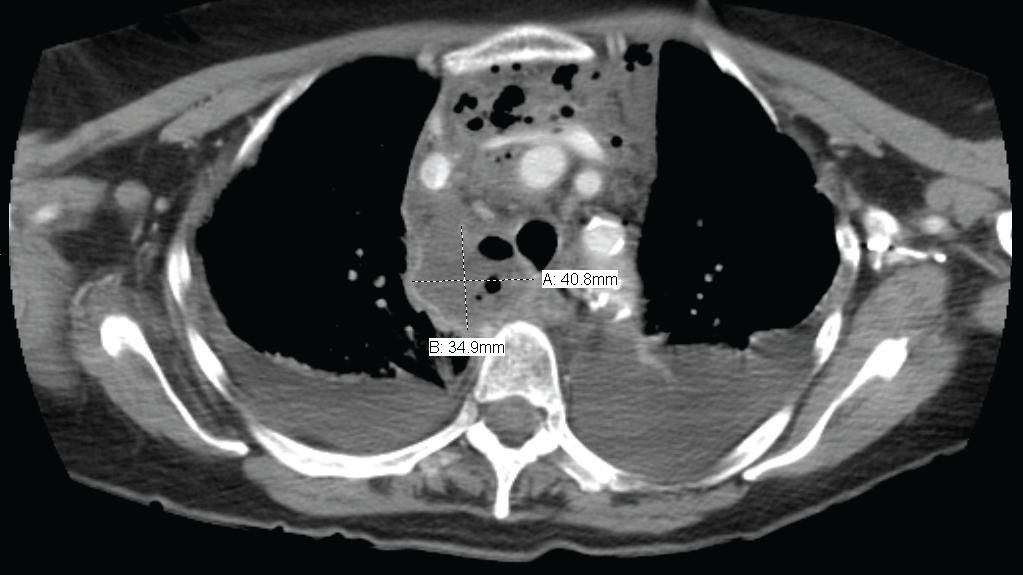

Figure 3 - A CT scan of the chest (horizontal view) obtained November 9, 2005, shows a fluiddensity structure, roughly measuring 3.5 & chi; 4.1 & chi; 6.3 cm, in the right posterior mediastinum.It is consistent with an abscess with extension into the anterior mediastinum between the superiorvena cava and the remainder of the central great vessels. Mass effect on the trachea is notedwith tracheal deviation to the left. Small bilateral pleural effusions are present with bibasilaratelectasis rather than consolidation.